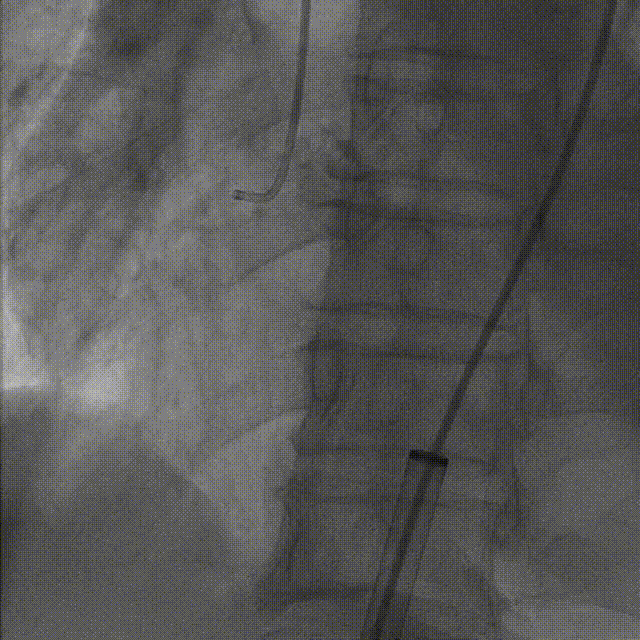

1.根据术前测量分析,采取右侧股动脉作为主入路,左股为辅入路,冠脉造影显示双侧冠脉灌注良好。

左冠造影

右冠造影

2.置入猪尾进行根部造影,造影可见主动脉根部大量钙化,瓣叶活动度低,冠脉灌注良好,中量反流。

根部造影